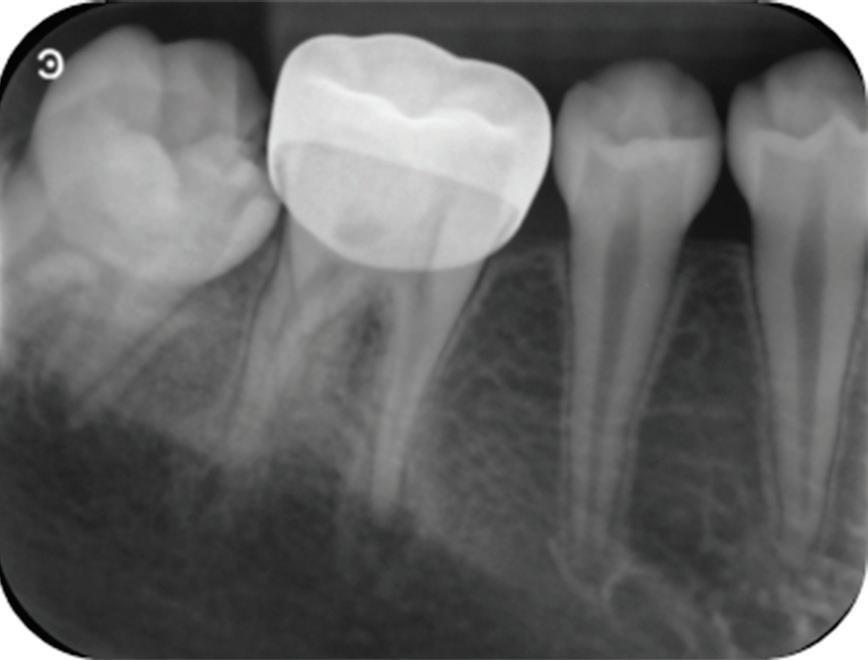

A healthy 10-year-old boy, accompanied by his mother, sought treatment of his mandibular right first molar because of pain in response to cold stimuli but reported no spontaneous pain in this tooth. Clinical examination revealed a carious lesion involving the occlusobuccal surfaces, and the tooth also appeared hypomineralized on the affected surfaces (Fig 1). The tooth responded positively to sensitivity tests, including the electric pulp test and cold test (Endo-Frost, Coltene), and there was no lingering pain or pain on percussion. A preoperative radiograph showed a large carious lesion extending to the pulp, incomplete root formation, and no pathologic periapical lesions (Fig 2). Therefore, the initial preoperative diagnosis was reversible pulpitis. The patient and parent were informed of possible pulp exposure, and VPT treatment after pulp exposure was explained in detail. Written consent for VPT was obtained from the parent.

deep caries, exposed pulp, and incomplete root formation but no pathologic periapical lesion.

Fig 2. Preoperative radiograph showing